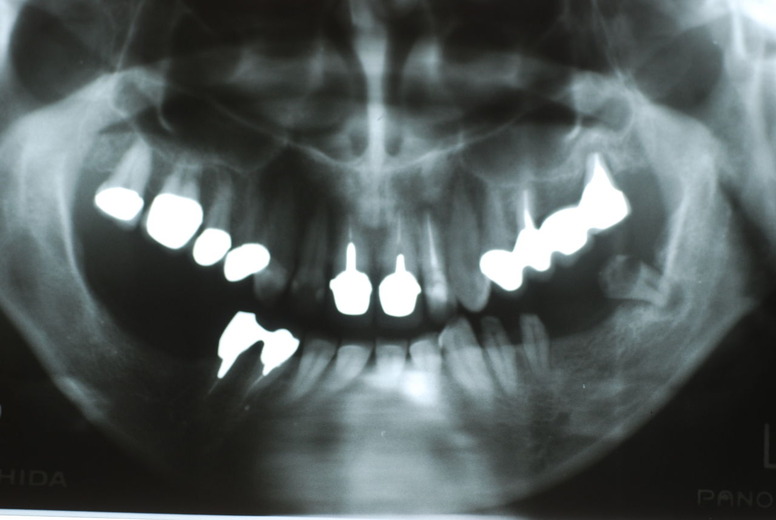

親知らずを取ることを嫌がる方が多いのですが、もし親知らずとその隣の14歳大臼歯の間に虫歯ができたり歯周病を罹患した場合、どれほど治療が大変で再発も起こりやすいか理解できない方がおおいのです。

隣の14歳大臼歯がひどい虫歯になり治療不可能になりつつある状態のレントゲン